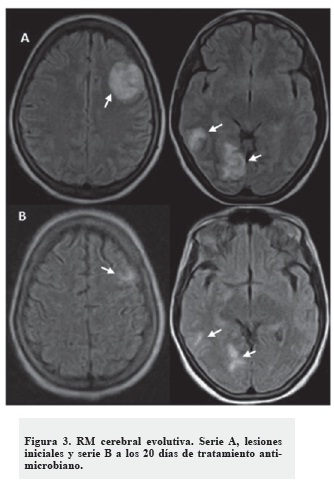

Se realizó una RM cerebral donde se observaron lesiones ligeramente hipointensas en T1 e hiperintensas en T2 con áreas de menor intensidad en su interior (frontal izquierda, occipital derecha y parietal posterior derecha), siendo la mayor frontal izquierda (23 x 21 mm), que no desplazaban las estructuras de la línea media ni producían herniaciones (Figuras 2 y 3, serie A). Las características imagenológicas de estas lesiones tampoco fueron concluyentes para un diagnóstico etiológico de las mismas.

Decidimos realizar una SPECT cerebral con 99mTc - MIBI donde no se observó captación patológica del radiofármaco en el estudio precoz el ni tardío (Figuras 2, serie B y C). Ante la negatividad de este estudio, diagnosticamos que las lesiones evidenciadas en TC y RM de cráneo correspondían a abscesos cerebrales. La paciente fue tratada con antimicrobianos de amplio espectro y en estudio evolutivo a los 20 días -RM cerebral-, se observó una gran mejoría de las lesiones encefálicas (Figura 3).